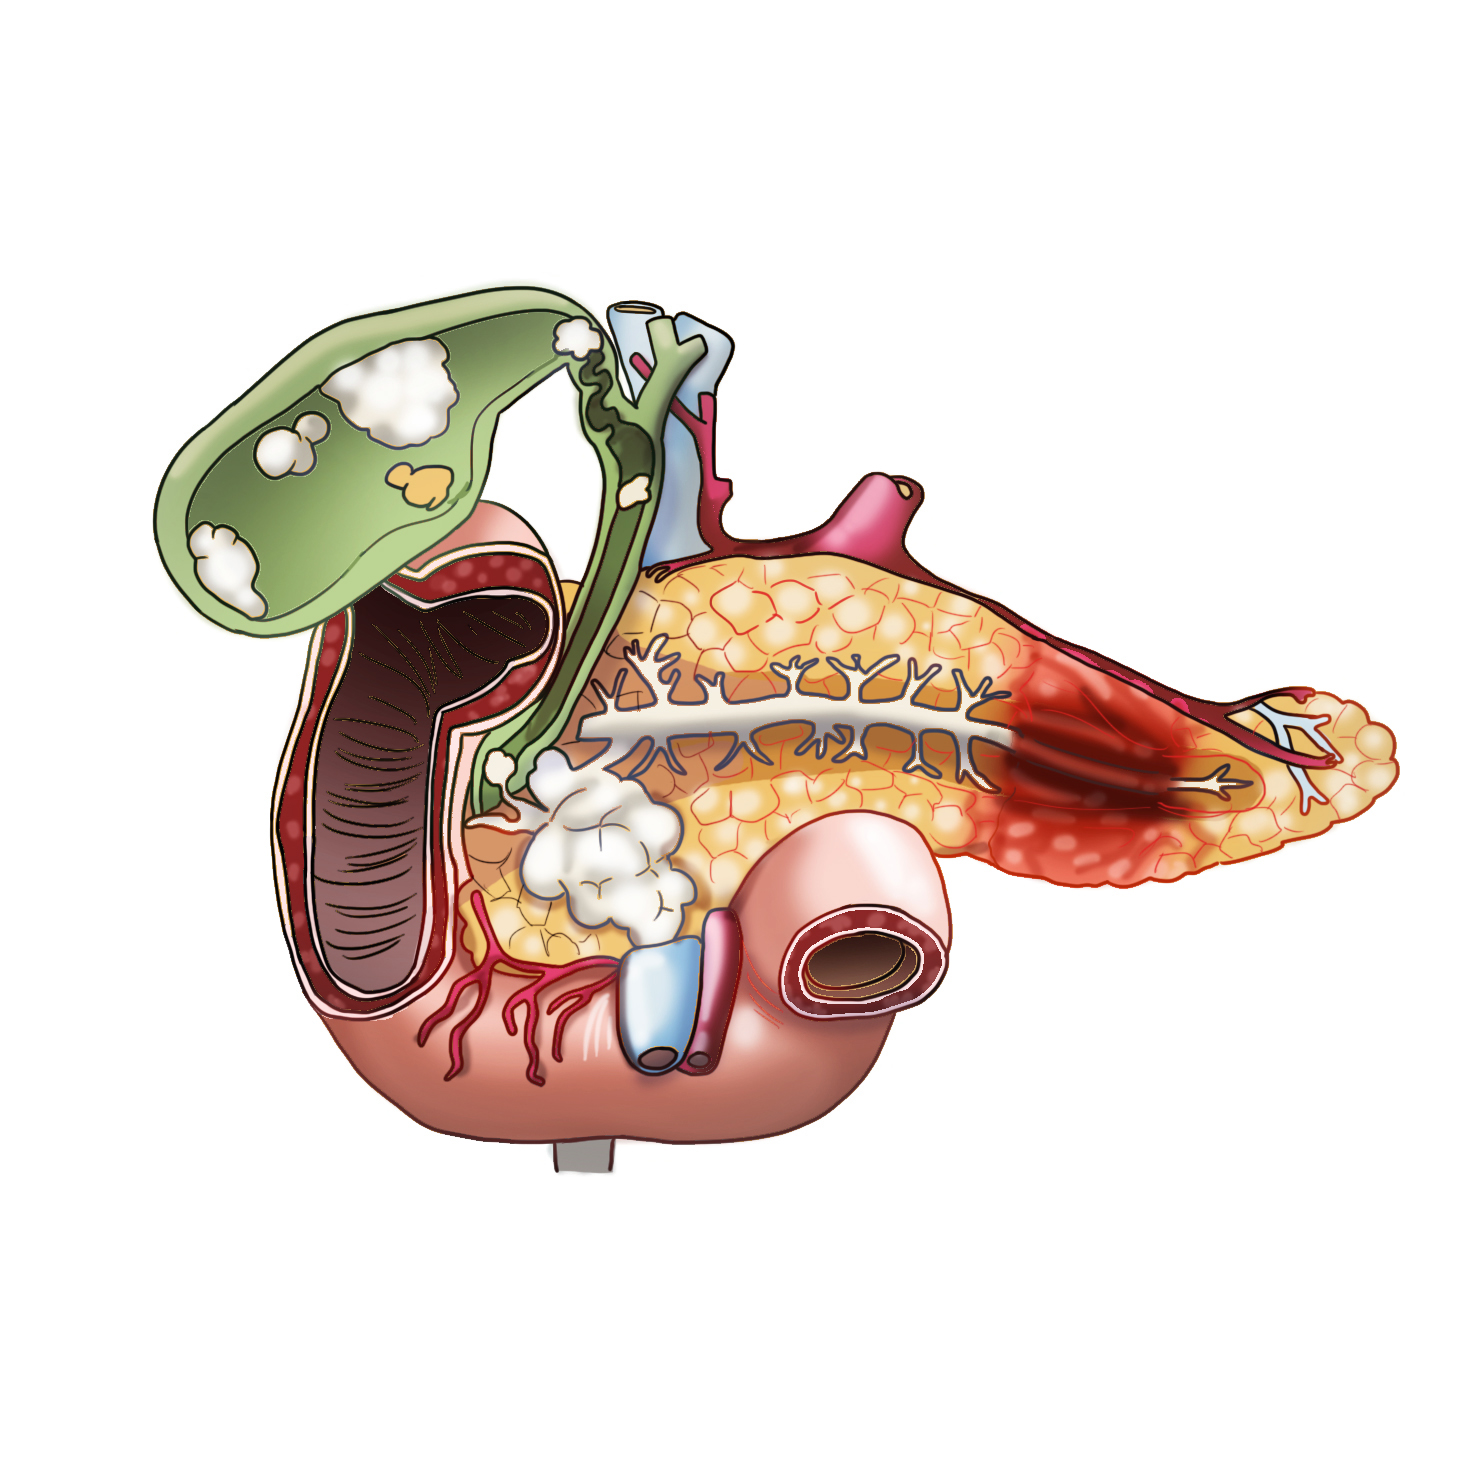

췌장세포에서는 췌액을 만들어 췌관을 통해 십이지장으로 분비하는데, 췌관이 십이지장으로 연결된 부위를 바터팽대부라고 합니다. 여기서는 췌장액 뿐만 아니라 간에서 만들어진 담즙도 함께 배출되는 통로로 췌장에 문제가 발생하면 담즙 배출 또한 함께 장애가 생길 수 있어 황달이 동반될 수 있습니다.

췌장은 외분비기능과 내분비기능을 함께 수행합니다. 췌장은 췌관을 통해 췌장액을 분비하는 외분비기능을 주로 수행하며, 여기서 분비된 췌장액은 담즙과 만나 소장으로 흘러들어가 소화를 도와주는 역할을 합니다. 췌장의 내분비기능은 랑게르한스섬에서 이루어지는데, 랑게르한스섬의 알파세포에서는 혈당을 높이는 글루카곤을 분비하고 베타세포에서는 혈당을 낮추는 인슐린을 혈중으로 분비하여 우리 몸의 혈당을 조절합니다.

췌장암은 조기 진단이 어려워 암 중에서 예후가 좋지 않은 것으로 알려져있습니다. 췌장암은 초기에 증상이 잘 나타나지 않고, 증상이 나타나더라도 식욕감소, 체중감소, 복통 등 비특이적인 증상이기 때문에 조기 진단이 어렵습니다.

또한 췌장의 위치가 후복막이고 주변에 혈관이 많이 존재해 진단 당시 이미 전이가 되어있을 가능성도 많습니다. 그러나 췌장암 중 머리쪽에 생긴 암은 황달이 나타날 수 있으므로 체부나 꼬리부분에 생긴 것보다는 빨리 발견될 수는 있습니다.